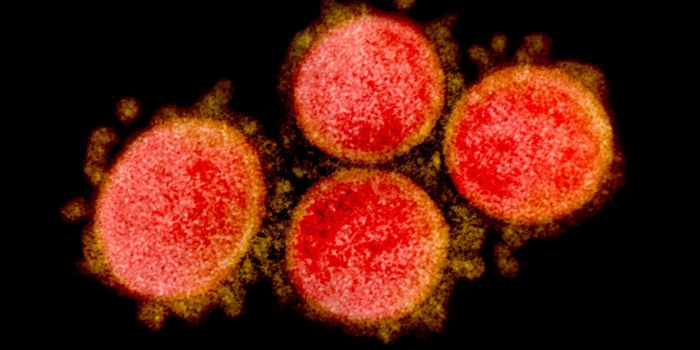

JUL 11, 2021MicrobiologyIn October 2020, what's now called the Delta variant of SARS-CoV-2 was first detected. It's now the most prevalent strai ...

NOV 01, 2021Cell & Molecular BiologyResearchers have learned a lot about the SARS-CoV-2 virus since the start of the COVID-19 pandemic. We know that he viru ...

MAY 06, 2020Cell & Molecular BiologyOnce thought to cause symptoms that primarily affect the respiratory system, there has been evidence that the virus can ...

SEP 07, 2021MicrobiologyThe world has rapidly become familiar with sarbecoviruses, two of which jumped to humans in recent years. The first was ...